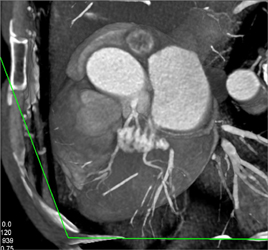

Normal Coronary Arteries